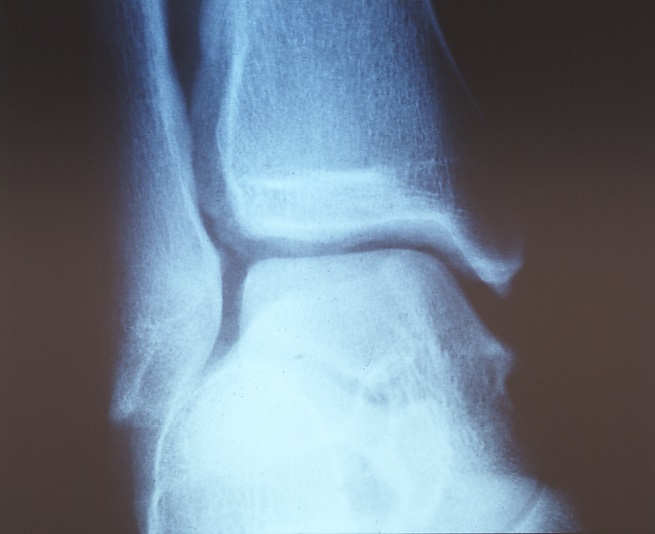

X-rays can be used to check for fractures, to check for spicules, to perform a stress X-ray to check for ligament loosening (Photos 3 and 4). Lately, MRI and ultrasound examination are adopted to diagnose in detail.

Photo 3: The ankle is preserved at a glance

Photo 4: The same ankle in the stress